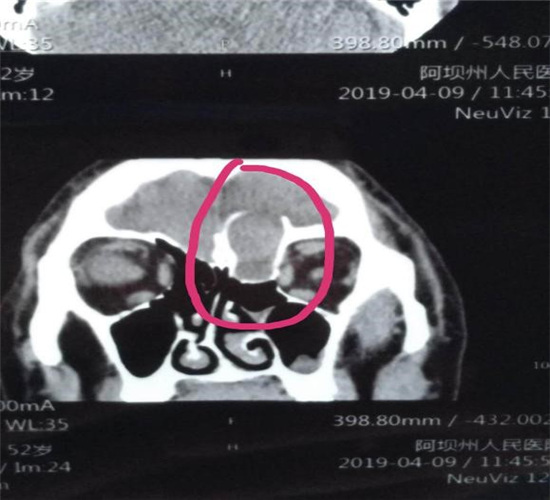

患者潘某,男,壤塘人,51岁。近3年来出现渐进性加重额部头痛、左眼胀痛及复视。入住五官科后行头颅ct发现鼻颅贯通性占位,颅底骨质破坏。

术前CT及MRI检查: